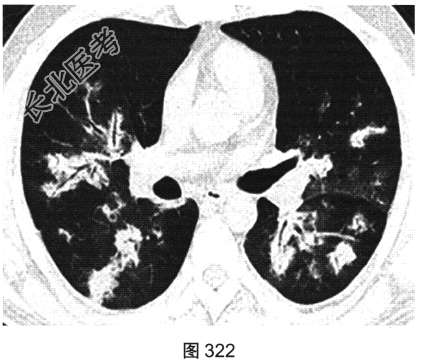

- [材料题] 患者男性,30岁,发作性咳喘3年,吸入冷空气后鼻塞、流黄白色脓涕,外院予环丙沙星治疗后症状缓解,其后鼻塞,夜间睡眠中喘憋反复发作;咯血、发热1周,以傍晚和夜间为著,体温最高为38.5℃,伴畏寒及周身疼痛,痰中带血,为鲜红色,伴胸痛、咳嗽,喘憋明显。胸部CT检查如图319~图324所示。

- 多项选择题2.该患者病变的主要分布特点为( )

A、肺中央分布为主

B、肺外周分布为主

C、支气管血管束周围分布为主

D、上肺分布为主

E、随机分布

F、下肺分布为主